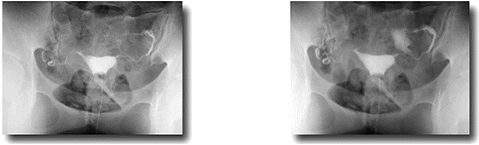

子宮卵管造影